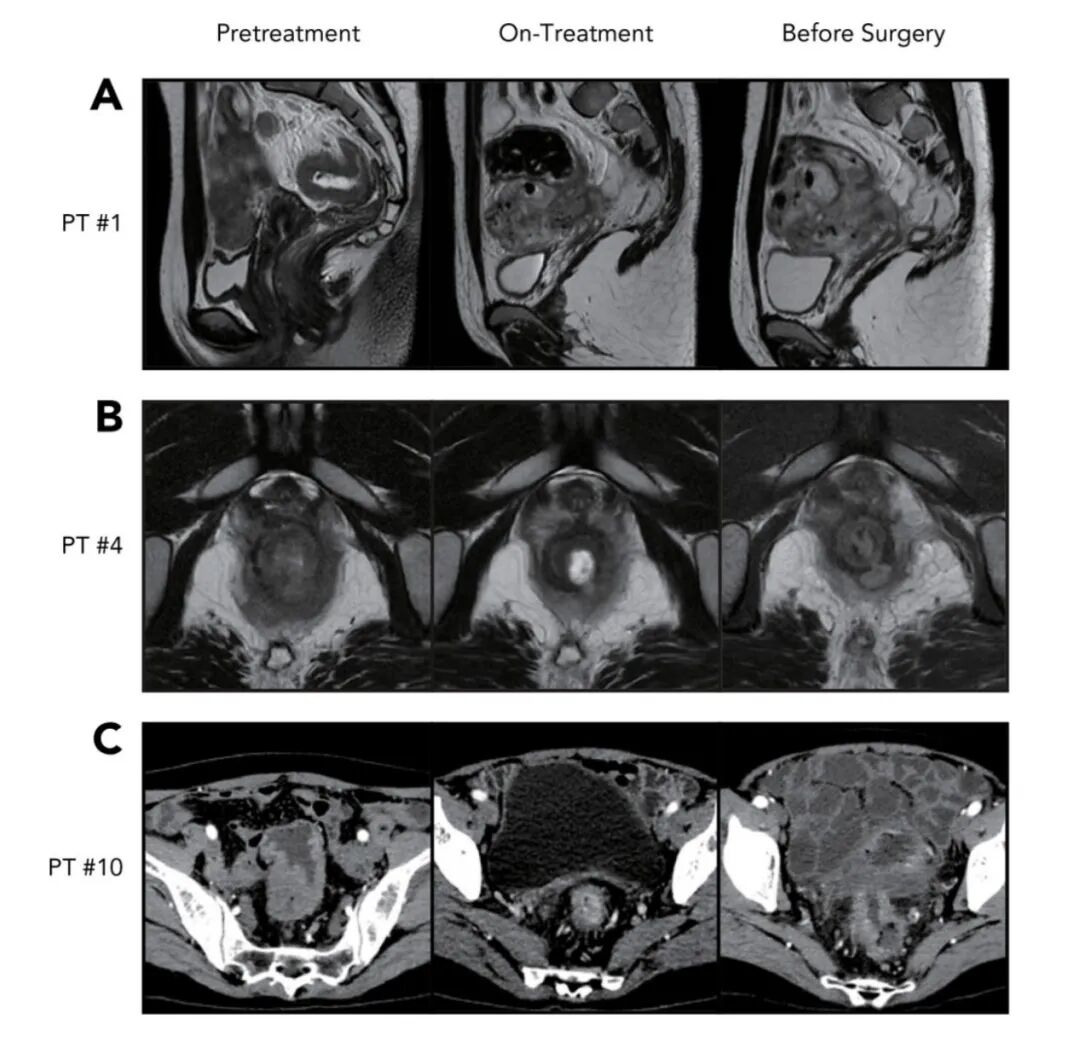

6.新辅助免疫检查点抑制剂治疗直肠癌的假性进展和假性残留单位:中山大学附属第六医院发表期刊:J Natl Compr Canc Netw(IF:13.4)

主要研究成果:13例MSI-H/dMMR的局晚期直肠癌患者,经过中位103天的免疫新辅助治疗后,影像学评估为:3例PD、1例SD、7例PR、2例CR;经病理评估,全部证实为完全缓解,其中3例出现假性进展、10例出现假性残留。进一步地病理分析发现,免疫治疗组的假性进展和假性残留主要包括纤维化、致密淋巴细胞和浆细胞漫润;新辅助化疗组没有出现假性进展或假性残留。本研究表明,接受免疫新辅助治疗易出现假性进展或假性残留,体现了采用多种技术综合评估疗效后做出治疗决策的重要性,以避免不必要的器官切除。

图片

图4. 3例假性进展患者影像